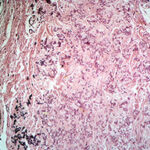

Histopathology. Histologic examination of the involved skin reveals considerable accumulations of swollen and irregularly clumped fibers staining like elastic fibers in the middle and lower thirds of the dermis; that is, they stain deeply black with orcein or Verhoetrs stain . Although normally elastic fibers do not stain with routine stains such as hematoxylin-eosin, the altered elastic fibers in pseudoxanthoma elasticum stain faintly basophilic because of their calcium imbibition. Staining for calcium with the von Kossa method also shows these fibers well. |

In the vicinity of the altered elastic fibers, there may be accumulations of a slightly basophilic mucoid material, which stains strongly positive with the colloidal iron reaction or with Alcian blue . The number of collagen bundles is reduced in such areas, and numerous reticulum fibers are seen on impregnation with silver . In some cases with pronounced elastic tissue calcification, a macrophage and giant cell reaction may be present . |

Histogenesis. Electron microscopic examination shows that the calcification occurs in normal-appearing elastic fibers . In some patients, especially in young persons, only some of the elastic fibers in the lower dermis are calcified, and the calcification is variable in degree. However, in adult patients, most elastic fibers show considerable calcification and, as a result, degeneration. Early calcification of elastic fibers consists either of diffuse granular deposits throughout the elastic fiber or of dense aggregates that may be located in the center or near the margin of the fiber (EM 5). With progression of the calcification, the elastic fibers ultimately become fully calcified, showing marked swelling and bizarre distortions. In addition, heavy calcium deposits may be seen in the ground substance adjacent to elastic fibers and free in the ground substance. The presence of calcified material outside of elastic fibers can be explained by the disintegration of completely calcified elastic fibers . |